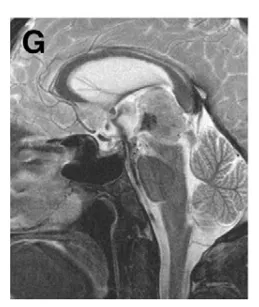

(G)术后第3天MRI显示造瘘处显著流空信号;ETV术后颅内压增高症状完全缓解